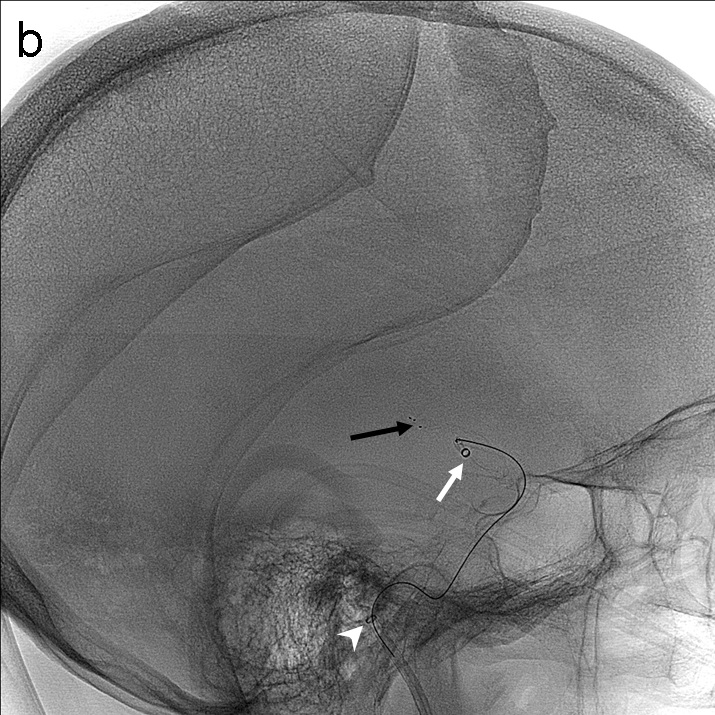

Tras la punción femoral derecha se asciende catéter balón FlowGate2 asistido por el catéter guía de asistencia punta Berenstein con guía de Terumo 0.035’’ para la cateterización de la arteria carótida común derecha y realización de estudio diagnóstico. Se obtienen series angiográficas en proyecciones anteroposterior y lateral de craneo que demuestran la presencia de trombo en el segmento M1 proximal de la ACM derecha (imagen 1). A continuación, mediante roadmap, cateterizamos la ACI derecha y realizamos un primer pase de trombectomía usando la técnica ADAPT a través del FlowGate2 con el AXS Catalyst 5 como catéter de aspiración, Trevo Pro 18 como microcatéter y con la microguía Asahi Chikai 0.014’’.